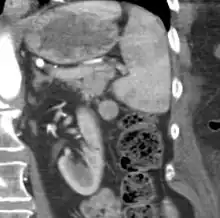

| CT scan of an accessory spleen (circular object in center of image) between the spleen and left kidney. | |

An accessory spleen is a small nodule of splenic tissue found apart from the main body of the spleen. Accessory spleens are found in approximately 10 percent of the population[1] and are typically around 1 centimetre in diameter. They may resemble a lymph node or a small spleen. They form either by the result of developmental anomalies or trauma.[2] They are medically significant in that they may result in interpretation errors in diagnostic imaging[2] or continued symptoms after therapeutic splenectomy.[1] Polysplenia is the presence of multiple accessory spleens rather than one normal spleen.